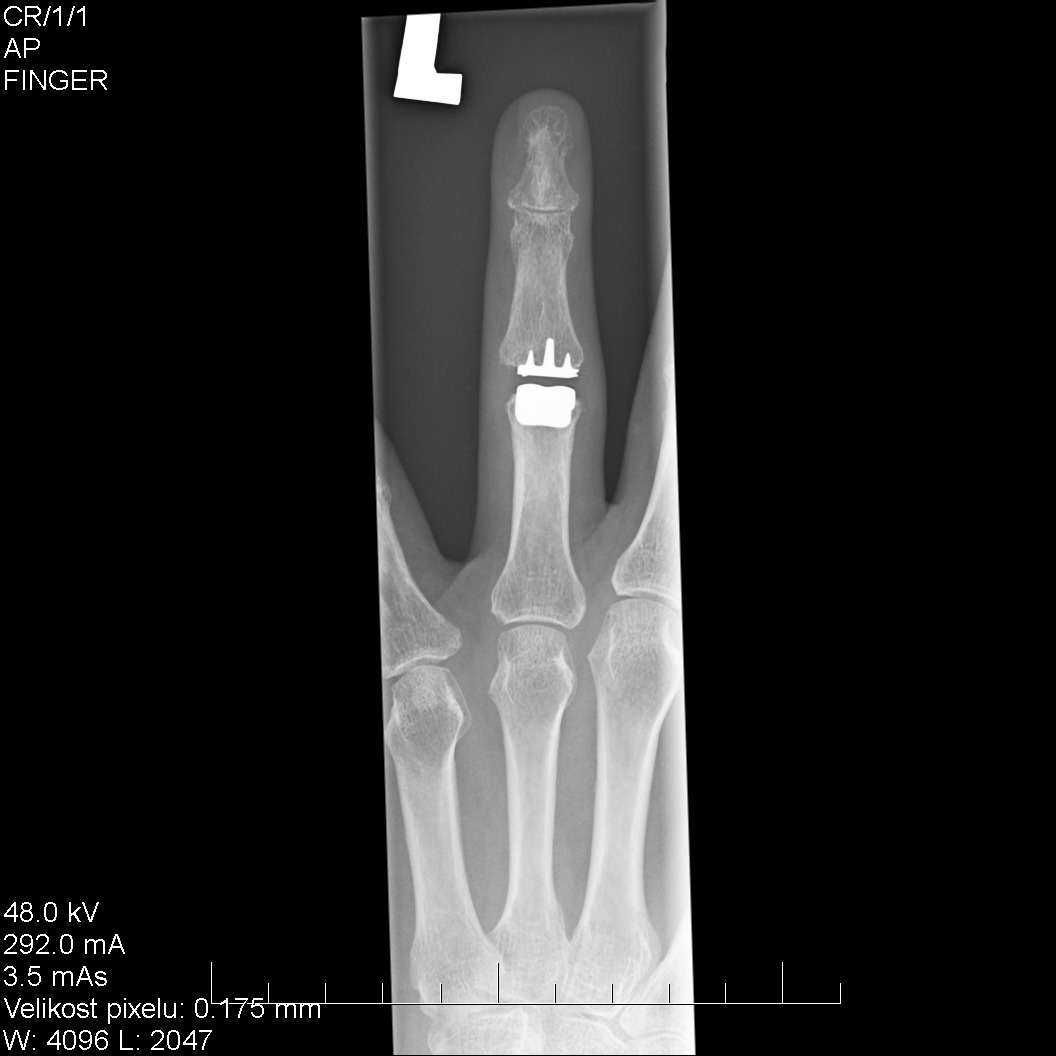

„Pokud jde o operaci samotnou, po technické stránce na ní nic tak zvláštního není, princip je stejný jako třeba u výměny kolenního kloubu, i když je tady samozřejmě všechno mnohonásobně menší. Tento zákrok je ale specifický zejména svou anatomickou lokalitou a četností, s kterou se v nemocnicích provádí,“ říká na úvod Martin Skládal, primář Ortopedického oddělení Uherskohradišťské nemocnice. Ve většině podobných případů se totiž problémy s klouby prstů řeší tzv. dézou, tedy srůstem kostí v určitém funkčním postavení. Tím ale samozřejmě kloub ztratí hybnost. „V tomto případě šlo o muže, který byl přivezen na traumatologii po pádu z výšky. Trpěl proto mnohačetnými zraněními a na problém s prstem si začal stěžovat až po několika měsících, kdy jsme objevili poúrazovou artrózu. Tento člověk se živí rukama, a proto jsme se rozhodli pro řešení, které by mu umožnilo v předchozí práci pokračovat, “ vysvětluje primář Skládal.

Kloubní náhrada, kterou v Uherskohradišťské nemocnici pacientovi operovali, má na kotvící straně ke kosti speciální povrch. Obrazně se dá říct, že pórovitá kost do něj přímo vroste, což zajišťuje mnohem lepší propojení s umělým kloubem. „Pokud by bylo potřeba takovouto náhradu někdy vyjmout a třeba vyměnit, bylo by nutné kost zlomit a kov vysekat. Po osmi měsících od operace ale můžeme říct, že implantát je pevně fixován. Vše proběhlo hladce a muž získal asi polovinu normálního rozsahu hybnosti zdravého kloubu a mohl se tak vrátit k běžné aktivitě,“ doplňuje primář Skládal.